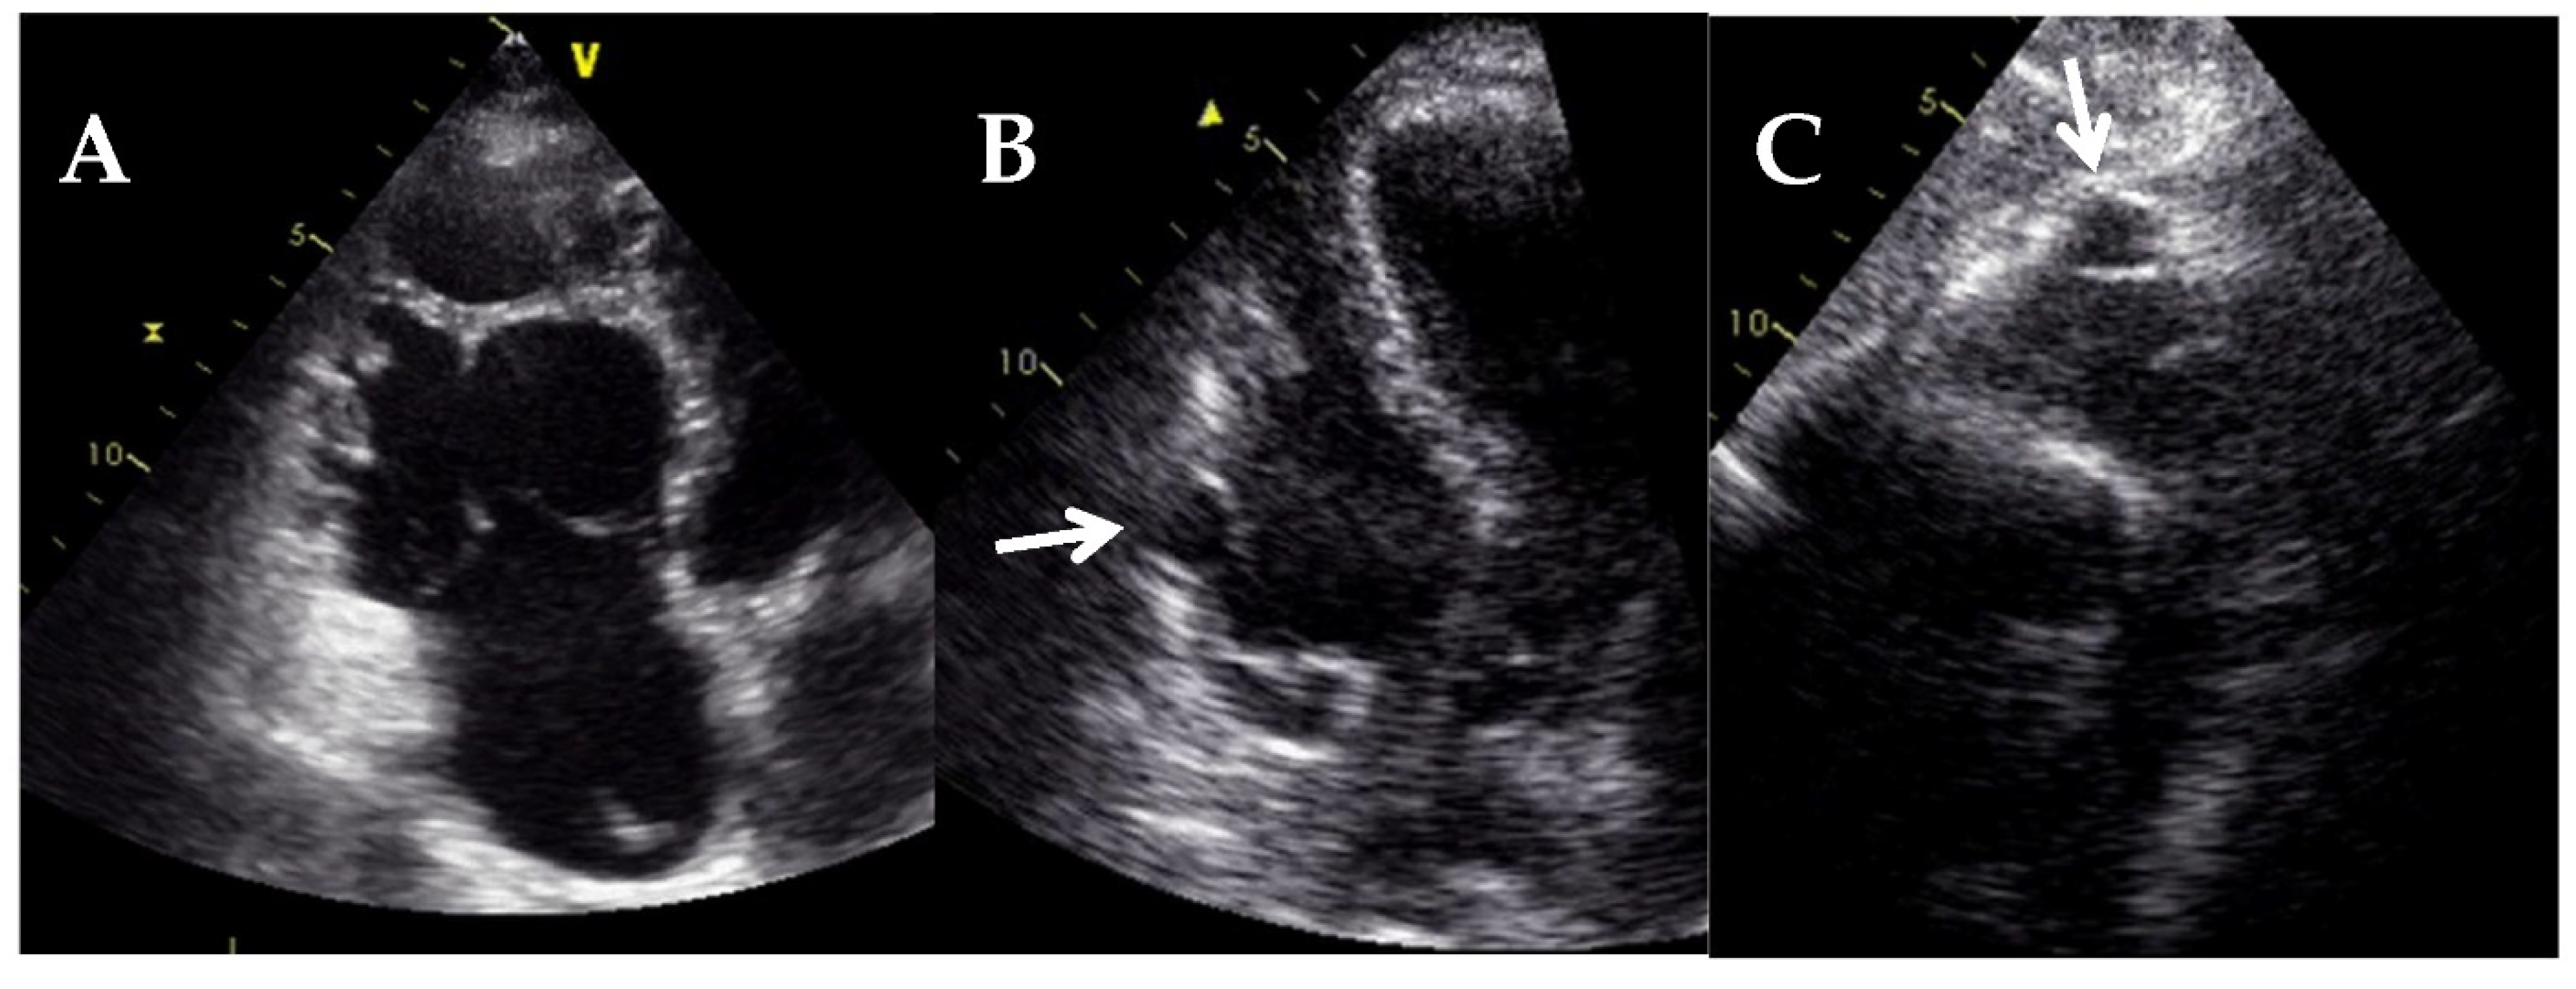

6. Left Ventricular Noncompaction

- Towbin, J.A.; Lorts, A.; Lynn, J. Left ventricular non-compaction cardiomyopathy. Lancet 2015, 22, 813–825. [Google Scholar] [CrossRef]

- Chin, T.K.; Perloff, J.K.; Williams, R.G.; Jue, K.; Mohrmann, R. Isolated noncompaction of left ventricular myocardium. A study of eight cases. Circulation 1990, 82, 507–513. [Google Scholar] [CrossRef] [Green Version]

- Bellavia, D.I.; Michelena, H.; Martinez, M.; Pellikka, P.; Bruce, C.J.; Connolly, H.M.; Villarraga, H.R.; Veress, G.; Oh, J.K.; Miller, F. Speckle myocardial imaging modalities for early detection of myocardial impairment in isolated left ventricular non-compaction. Heart 2009, 96, 440–447. [Google Scholar] [CrossRef]

- Tarando, F.; Coisne, D.; Galli, E.; Rousseau, C.; Viera, F.; Bosseau, C.; Habib, G.; Lederlin, M.; Schnell, F.; Donal, E. Left ventricular non-compaction and idiopathic dilated cardiomyopathy: The significant diagnostic value of longitudinal strain. Int. J. Cardiovasc. Imaging 2016, 33, 83–95. [Google Scholar] [CrossRef]